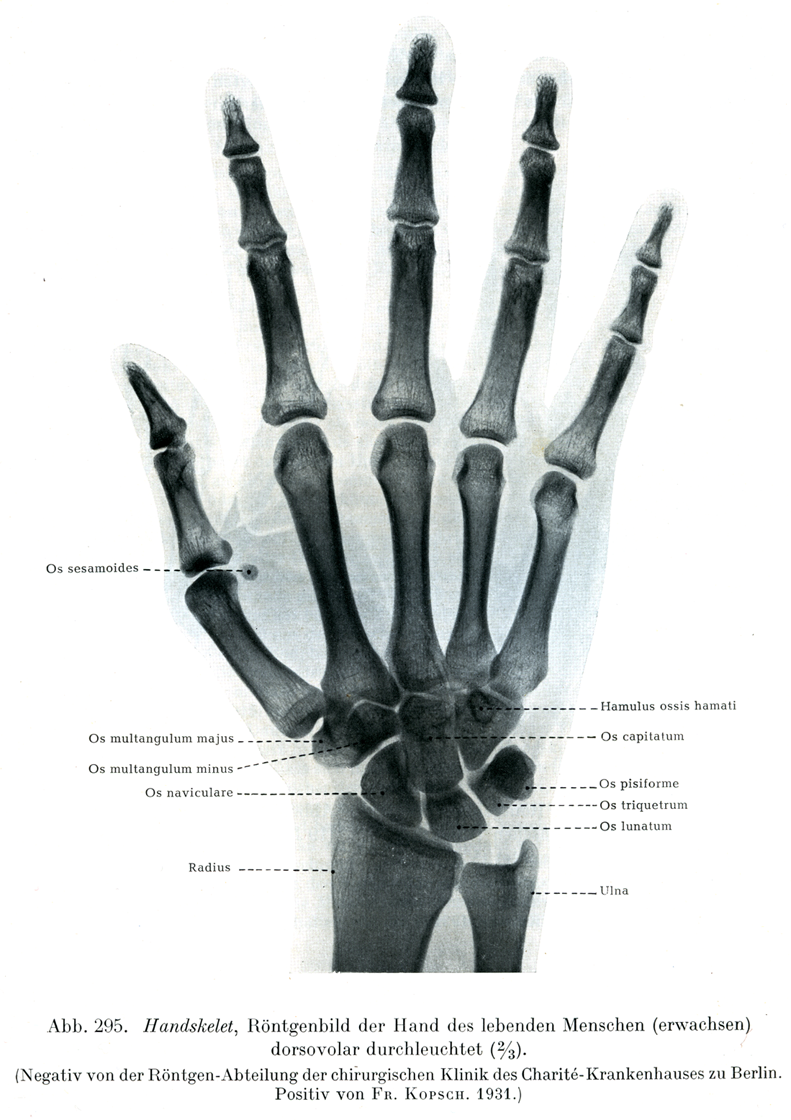

図295

手の骨格

生体(成人)の手のX線像.背掌照射(

2

/

3

)